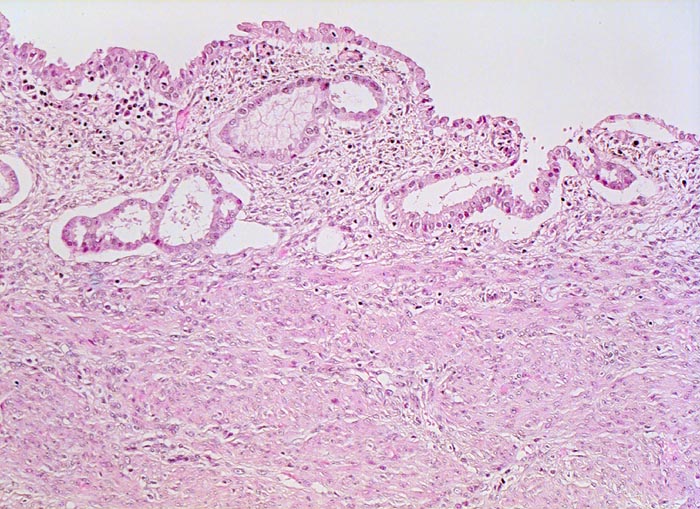

Endometrioide Karzinome bestehen aus tubulären Drüsen, welche von einem mehrreihigen Epithel ausgekleidet werden. Schleim ist meist nicht oder nur apikal in den Zellen vorhanden. Die Ausdehnung der soliden Areale und die zytologischen Atypien bestimmen den Differenzierungsgrad (low-grade versus high-grade). Metaplastisches Plattenepithel findet sich häufig in endometrioiden Karzinomen und hilft bei der Abgrenzung von anderen Subtypen. Das endometrioide Karzinom kann sich innerhalb von Adenomyoseherden im Myometrium entwickeln (> 4482). In diesen Fällen kann die Bestimmung der Infiltrationstiefe erschwert sein.

• Endomyometranes Gewebsfragment.

• Die rechte Seite des Uteruskavums wird ausgekleidet von flachem atrophem Endometrium. Im Cavum liegt ein Blutkoagel mit nekrotischem Detritus nach vorausgegangener diagnostischer Utersukurettage.

• Anstelle des Endometriums findet sich in der linken Hälfte des Uteruskavums ein Adenokarzinom bestehend aus architektonisch komplexen Drüsen. Die Drüsen liegen teils dos à dos ohne erkennbares Stroma zwischen zwei Drüsenschläuchen.

• Tumorzellverbände infiltrieren die glatte Muskulatur des Myometriums.

• Tumordrüsen ausgekleidet von mehrreihig angeordneten Tumorzellen mit hyperchromatischen polymorphen längsovalen Tumorzellkernen mit zahlreichen Mitosen. Die Morphologie der Tumordrüsen erinnert an proliferatives Endometrium.

• Anmerkung: Typischerweise ist das endometrioide Karzinom des Uterus als Folge des ursächlichen Hyperöstrogenismus assoziiert mit einem hyperplastischen Endometrium (siehe Präparat 148). Im Kurspräparat erscheint hingegen das nicht-neoplastische Endometrium nach vorausgegangener Kurettage atroph. Atrophes Endometrium findet sich sonst charakteristischerweise neben serösen Endometriumkarzinomen postmenopausaler Patientinnen. Das sollte der Kliniker dem Pathologen mitteilen: